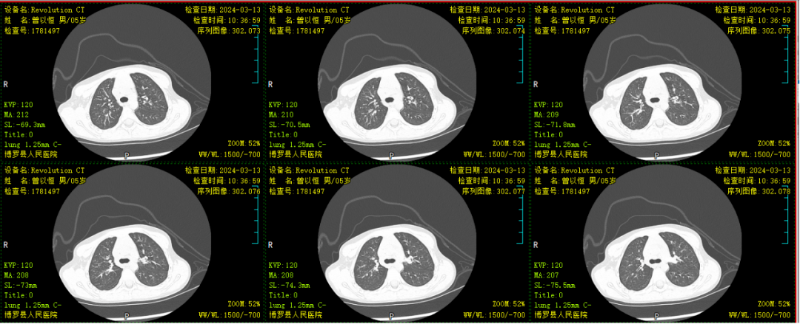

文章配圖

△完善胸部CT示:左肺感染,伴左肺上葉部分實變。

結合胸部CT特點,符合行電子支氣管鏡檢查指征,予行肺泡灌洗治療。肺泡灌洗液送檢提示肺炎支原體感染,予加用阿奇霉素抗感染治療。行電子支氣管鏡肺泡灌洗治療一周后,患兒無發熱,咳嗽較前明顯好轉,聽診肺部無啰音,復查胸部CT顯示病灶較前明顯吸收,予帶藥出院。